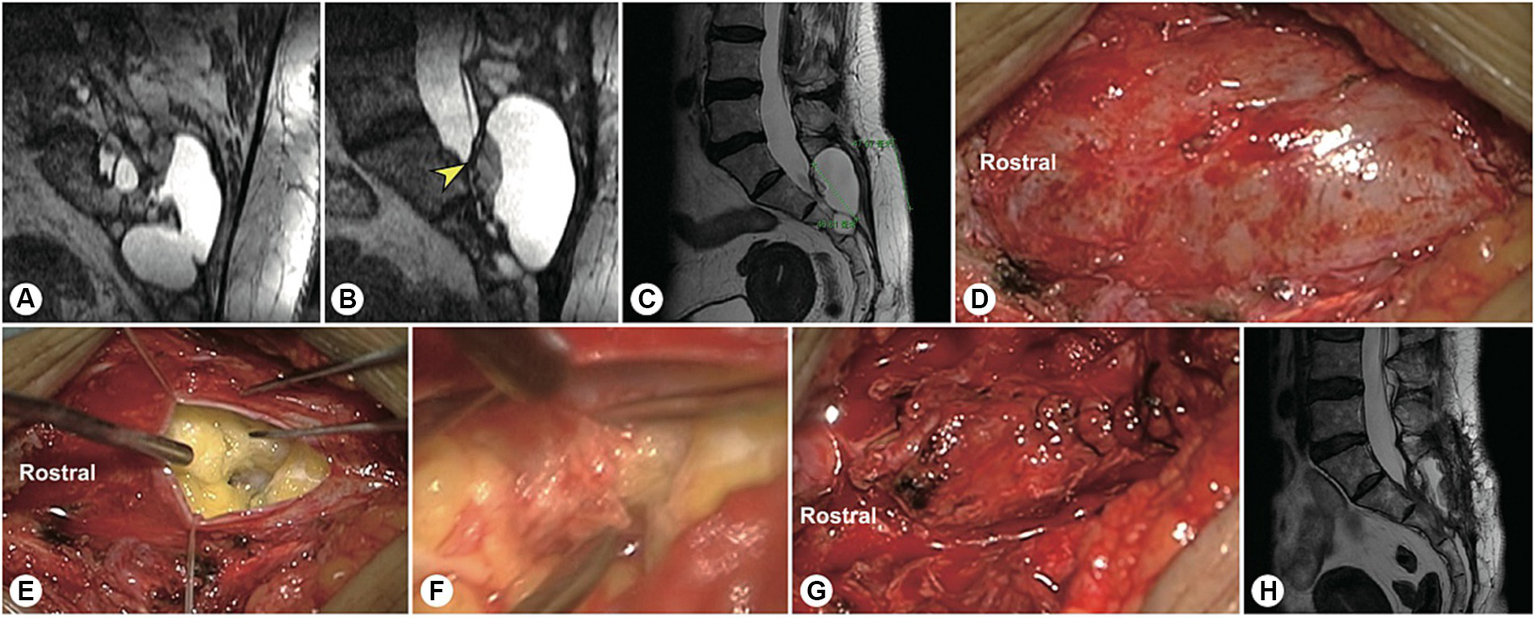

Figure 3

A representative patient with a fistula-type cyst. (A,B) Preoperatively, reconstructed MR image showing a fistula between the dural sac and the cyst (yellow arrowhead). (C) A 5 cm precise minimally invasive incision was designed (yellow line segment). (D) Intraoperatively, a fistula-type cyst was found, and there was no nerve root. (E) The cyst wall was dissected and turned over. (F) The cyst neck was ligated. (G) Follow-up MRI showed that the cyst had disappeared and that there was no recurrence.